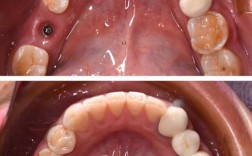

种植牙植骨的成功率受多种因素影响,但总体而言,随着医疗技术的进步和材料的发展,植骨后种植牙的成功率已保持在较高水平,临床研究表明,植骨后种植体的5年成功率可达85%-95%,10年成功率约为80%-90%,这一数据与直接种植牙的成功率(90%-98%)相比略低,但仍属于较高范围,能够满足大多数患者的功能与美观需求。

成功率的具体数值因植骨材料、患者自身条件、手术技术等因素存在差异,自体骨移植的骨结合效果最佳,5年成功率可达90%以上;而人工骨或异体骨移植的成功率可能在85%-95%之间,若患者存在糖尿病、吸烟等风险因素,成功率可能降至70%-80%,骨缺损的范围和位置也会影响结果,前牙区因美学要求高、骨量相对薄弱,植骨成功率略低于后牙区;而大范围骨缺损(如上颌窦提升、骨牵引成骨等复杂手术)的成功率相对较低,约80%-85%。